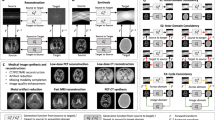

The imaged anatomical structure of each patient is manually segmented with masks into three regions: bony, soft, and mixed regions. An example of the three regions superimposed on an MRI image is shown Fig. 1A. The bony region contains the cortical and cancellous bone tissues, while the soft region contains all soft tissues. For the bony region, a mask is defined at the edge of the cortical bone with approximately 1 mm margin left out. A margin of approximately 2–3 mm surrounding the bony tissue is not included within the soft region. Margins are generated automatically by expansion or reduction of the mask. The mixed region represents the region between the above two margins. Then voxels within the same region are grouped together for determining the prediction model for the region.

When necessary, an excluded region, as shown in Fig. 1B, is drawn to select misaligned anatomical structures due in large part to changes during the elapse time between MRI and CT acquisitions. To obtain the correct correlation between MRI intensity values and the CT number of each voxel, voxels from the excluded region are not included in the training data used to determine or evaluate our prediction model.

An example of the pCT image is shown in Fig. 3 with the axial view of the patient’s MRI (MR1 and MR2) and CT images at the same slice. We see that the pCT image (Fig. 3D) closely matches the rCT (Fig. 3C). Noticeable structural differences are predominantly in the soft tissues, specifically the bladder and bowel. Similar differences are also observed between the rCT (Fig. 3C) and MRI images (Fig. 3A,B). Other minor differences are observed at the muscle-fat tissue and bony-tissue interfaces. These can be mostly attributed to the extended duration between the acquisition times of MRI and CT images. Therefore, the region with major structural differences (e.g. bladder and bowel due to daily changes) between the CT and MRI images are segmented as the excluded region and omitted in determining the prediction model or the MAE calculations.